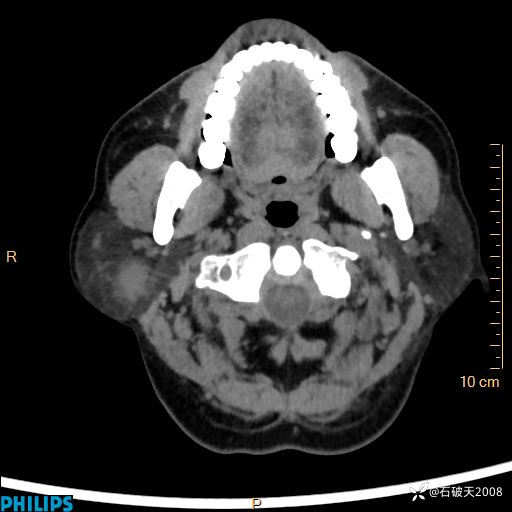

病例分享:颈部占位,一周后公布病理

男 57岁 主 诉:发现右侧颌下肿物1月余。

现病史:1月余前家属发现右侧颌下肿物。局部皮肤无红肿、热痛,无吞咽困难,无异物感,无恶心、呕吐,无头痛、头晕,无胸闷、胸痛,无发热、咳嗽、咳痰及呼吸困难。于我院行体表肿块彩超检查(2024.03.15我院)示:右侧耳下皮下软组织内低回声,未治疗。今为进一步治疗门诊以“腮腺肿瘤”为诊断收住我科,发病来患者神志清,精神可,饮食、睡眠及大小便正常,体重无明显下降。

平扫